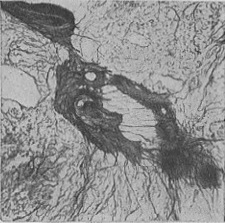

Рідше зустрічається дифузний миеломатоз, коли дифузне розростання мієломних клітин не супроводжується розвитком вузлів. При цій формі тканина кісткового мозку на розрізі має строкатий вигляд, містить рожево-білі, сіро-червоні поля, спостерігається дифузний остеопороз; в рідкісних випадках розсмоктування кісткової тканини є незначним. При гістологічному дослідженні кісткового мозку виявляють розростання ретикулярних клітин різної величини і форми, часто плазматического типу з базофильной цитоплазмою, багатою РНК; зустрічаються гігантські багатоядерні клітини. В області розростань завжди виявляється ніжна мережа аргірофільних волокон (рис. 7).

![]() Рис. 7. Миеломный вузол в кістковому мозку з вираженою мережею аргірофільних волокон (імпрегнація сріблом за Футу).  |